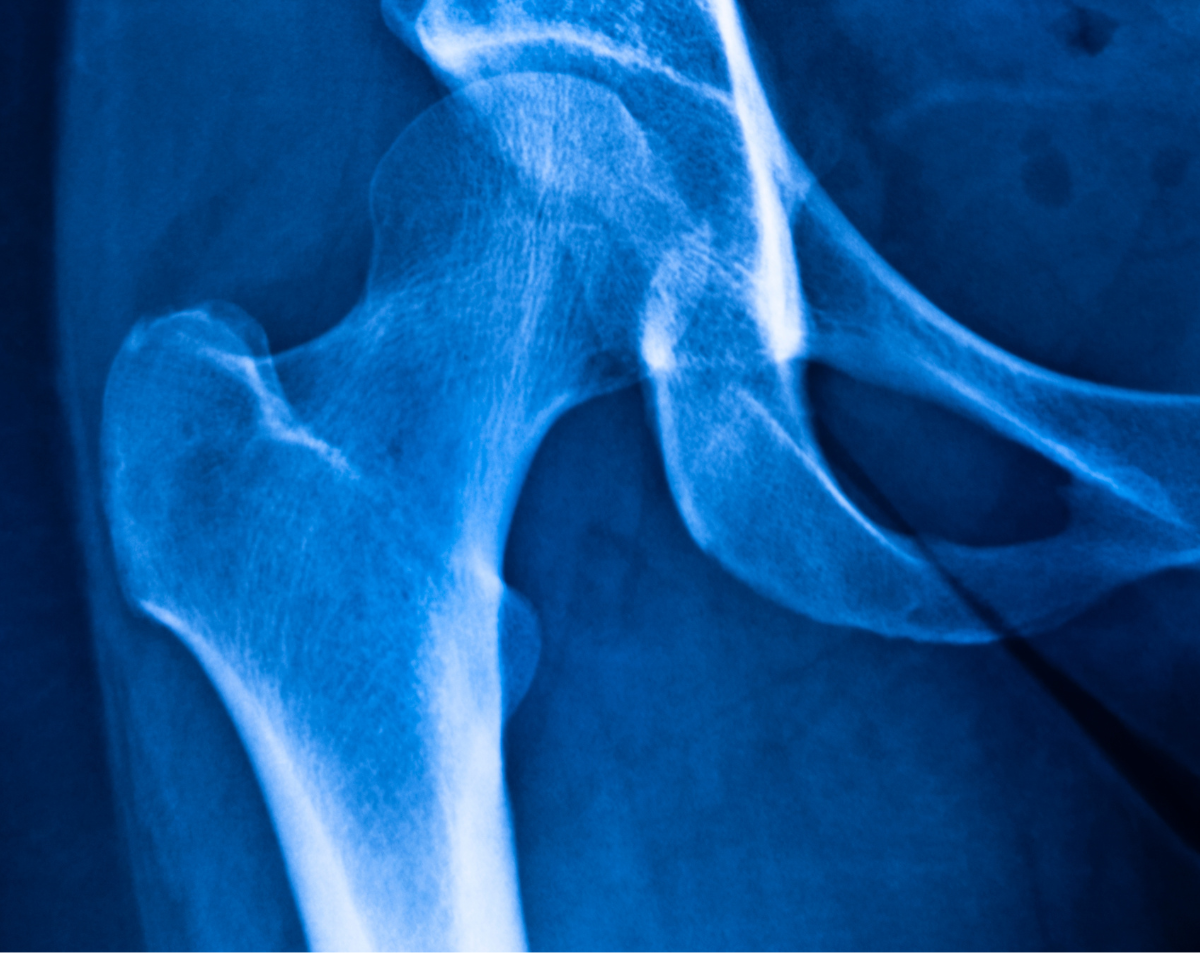

A mobile femur X-ray provides clear images of the thigh bone, hip, and knee connection. Therefore, it helps your physician identify:

Fractures or breaks caused by accidents, falls, or sports trauma

Stress fractures common in athletes or active individuals

Bone healing progress after surgery, casting, or previous injury

Bone tumors or abnormal growths in the thigh bone

Infections that may weaken the bone structure

Arthritis or joint degeneration affecting nearby hip or knee joints